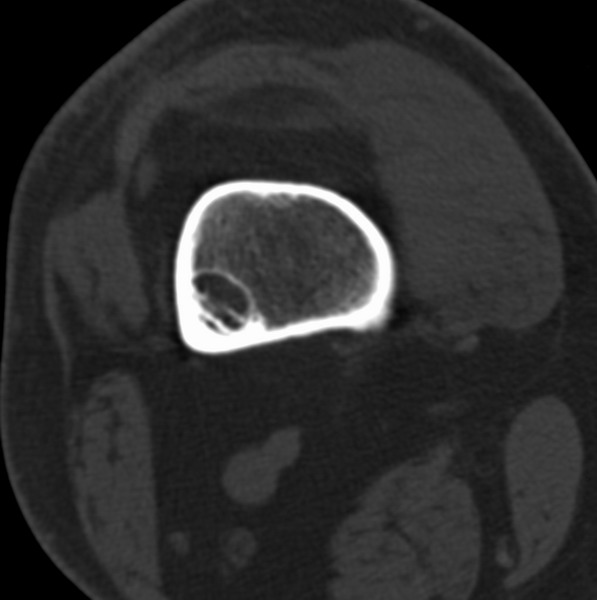

标题: CT21959:骨肿瘤请会诊。

右侧膝关节疼痛一月

男、48

股骨下段、胫骨上段。

1、股骨干骺端病变考虑干骺端纤维性皮质缺损愈后(非骨化性纤维瘤)改变,胫骨近端内生骨瘤;

2、骨关节炎,骨质增生,股骨外侧髁退变性囊肿(关节面软骨下囊肿);

支持非骨化性纤维瘤

非骨化性纤维瘤